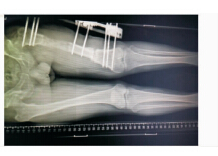

图 1 患者,男性,47岁,左股骨骨折术后6月

图 2 左股骨骨髓炎X线片

图 7 术后X线片